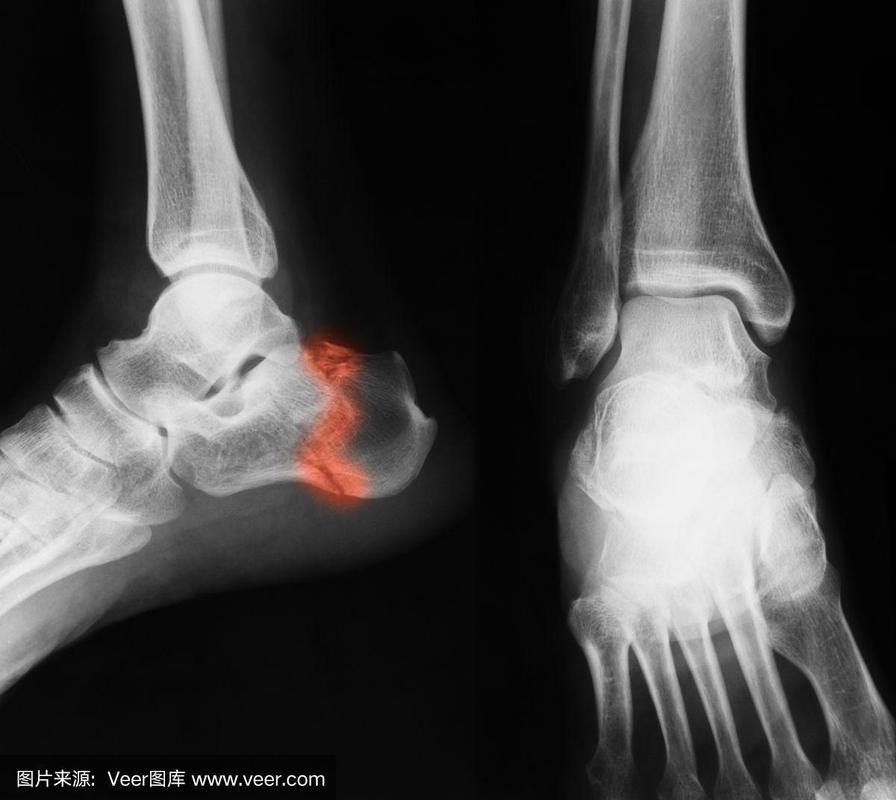

踝,x光片,跖骨,跟骨,手舟骨

跟骨骨折关节镜下微创治疗